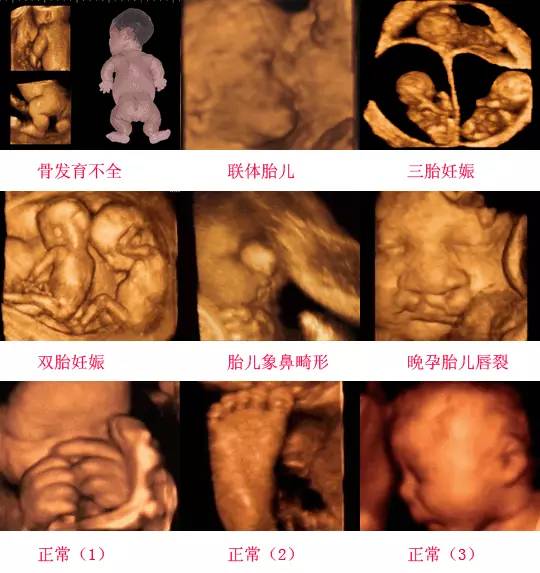

四維彩超是一種先進(jìn)的醫(yī)學(xué)影像技術(shù),通過實時觀察胎兒在母體內(nèi)的活動情況,為醫(yī)生提供了豐富的診斷信息,在四維彩超下,我們可以清晰地觀察到胎兒的蛋蛋(睪丸)的形態(tài)、位置和大小等特征,胎兒蛋蛋是男性生殖系統(tǒng)的重要組成部分,對于胎兒的生長發(fā)育具有重要意義。

在四維彩超下,胎兒蛋蛋呈現(xiàn)出特定的形態(tài)和外觀,通常情況下,胎兒蛋蛋呈現(xiàn)出圓形或橢圓形,表面光滑,內(nèi)部回聲均勻,隨著胎兒的發(fā)育,蛋蛋會逐漸增大,并呈現(xiàn)出明顯的性別特征,醫(yī)生可以通過四維彩超技術(shù),對胎兒蛋蛋的大小、形態(tài)和位置進(jìn)行評估,以判斷胎兒生殖系統(tǒng)的健康狀況。

胎兒蛋蛋的發(fā)育是一個復(fù)雜的過程,受到多種因素的影響,在胎兒發(fā)育的早期階段,蛋蛋位于腹腔內(nèi),隨著胎兒的生長發(fā)育,蛋蛋逐漸下降至陰囊,這個過程受到激素、遺傳和環(huán)境等多種因素的影響,在四維彩超的觀測下,我們可以實時了解胎兒蛋蛋的發(fā)育過程,及時發(fā)現(xiàn)異常情況并采取相應(yīng)的治療措施。

四維彩超技術(shù)在評估胎兒蛋蛋發(fā)育方面具有重要意義,通過四維彩超,醫(yī)生可以實時觀察胎兒蛋蛋的形態(tài)、位置和大小等特征,了解胎兒生殖系統(tǒng)的發(fā)育情況,四維彩超還可以幫助醫(yī)生發(fā)現(xiàn)可能的異常情況,如睪丸未降、睪丸囊腫等,為及時采取治療措施提供依據(jù)。